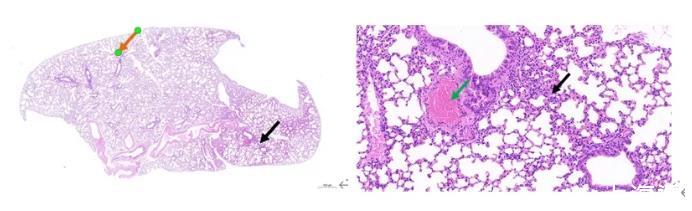

图5:对照组肺脏组织

肺脏组织的被膜结构清晰;肺脏实质为肺内支气管各级分支及其终末的大量肺泡,灶性肺泡壁轻度增厚(黑色箭头),肺泡间隔增宽;各级支气管结构无明显异常;少量血管周围结缔组织排列疏松(橙色箭头);少量血管淤血(绿色箭头);未见明显的炎性细胞浸润。